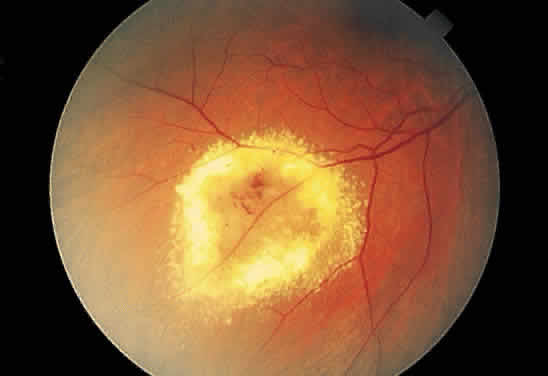

Fibrous tissue may originate from the choroid and proliferate through breaks in Bruch's membrane into the subpigment epithelial or subretinal spaces,4 hence the white appearance of disciform macular degeneration (Fig. 16). Fibrous tissue also may originate from fibroblasts located in the adventitia of retinal vessels and may contribute to the white appearance of vascularized membranes (Fig. 17A), such as those seen in proliferative diabetic retinopathy (see Fig. 17B) or arterioles after vascular occlusion (see Fig. 6). The accretion of collagen in the wall of the vessel in arteriolosclerosis may thicken the vessel wall (see Fig. 5) and alter the color of the blood column to a copper or silver color. Injury to the pigment epithelium results in scar formation (Fig. 18). Collagen deposition from pigment epithelium metaplasia may be identified by the presence of pigment within a scar (Fig. 19). Injured nonpigmented epithelium may undergo similar fibrous metaplasia and may contribute to the formation of membranes such as cyclitic membranes in the region of the ciliary body.

Fig. 16. Fundus photograph of a disciform macular scar, white because of fibrosis and atrophy of the pigment epithelium. A broad, C-shaped, fresh hemorrhage within the sensory retina surrounds it.